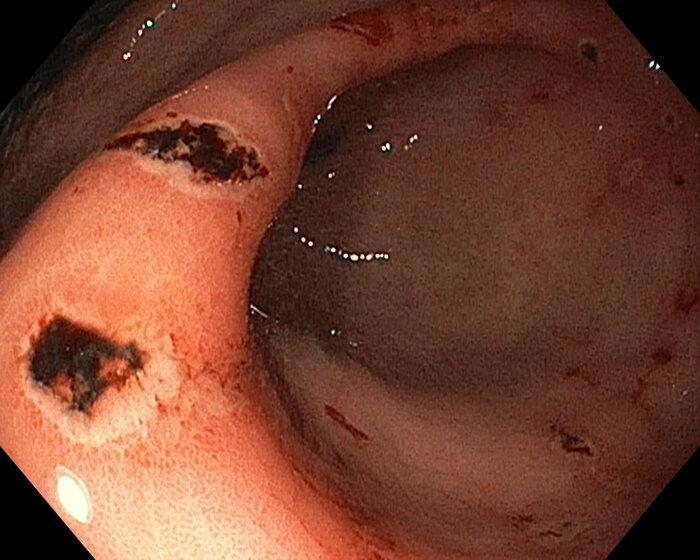

В качестве примера: на фото эндоскопическая картина химического ожога слизистой желудка, осложнившегося кровотечением. Пациентка была доставлена ко мне на гастроскопию после того, как отобедала с тарелкой, помытой азелитом. Тарелку плохо ополоскали после ПАВа. После недели лечения выписана домой в удовлетворительном состоянии, через месяц всё зажило.